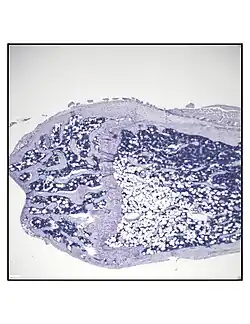

In order to understand the physiology of BMAT, various analytic methods have been applied. BMAds are difficult to isolate and quantify because they are interspersed with bony and hematopoietic elements. Until recently, qualitative measurements of BMAT have relied on bone histology,[51][52] which is subject to site selection bias and cannot adequately quantify the volume of fat in the marrow. Nevertheless, histological techniques and fixation make possible visualization of BMAT, quantification of BMAd size, and BMAT's association with the surrounding endosteum, milieu of cells, and secreted factors.[53][54][55]